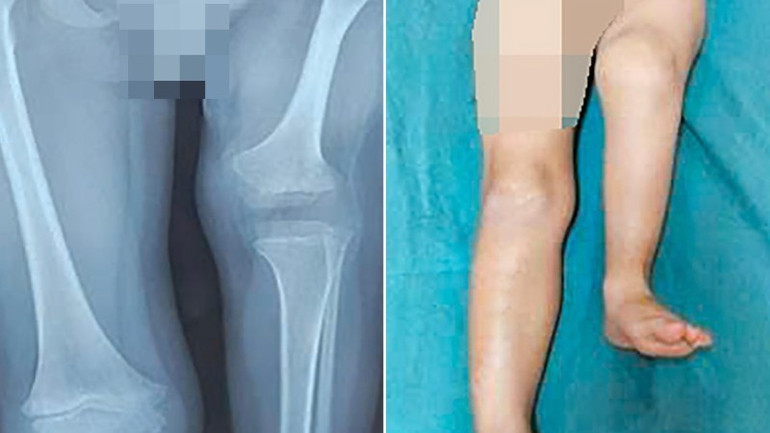

Chân trái của bệnh nhi thời điểm nhập viện.

Tại Bệnh viện Nhi Trung ương, thời điểm nhập viện xương đùi trái của trẻ chỉ đạt gần một nửa chiều dài so với bên lành; khớp gối cứng gấp, không thể duỗi hoàn toàn. Khi đặt hai chân song song, bàn chân trái chỉ ngang mức giữa cẳng chân phải, gây chênh lệch chiều dài chi nghiêm trọng và ảnh hưởng lớn đến sinh hoạt hằng ngày.